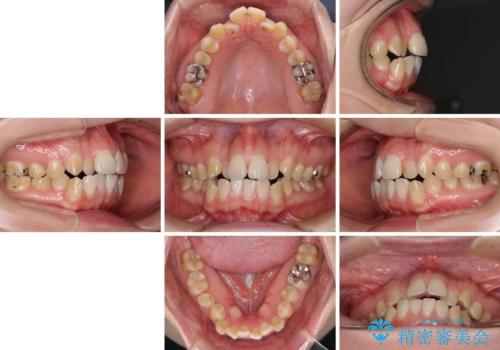

舌突出癖による開咬 舌のトレーニングを行いながら咬み合わせを改善

- 前歯のデコボコを気にして来院された患者様です。

前歯のデコボコはもちろん気になるところですが、舌の突出癖により上下前歯が非接触となっている状態でした。

上下前歯が非接触である開咬は、インビザラインによる治療がお勧めではありますが、しっかりと使う自信がないとのことで、ワイヤー装置にて治療を行うこととしました。

デコボコはあっという間に改善されましたが、開咬の改善に時間がかかりました。

舌の突出癖改善のトレーニングをしっかりと行っていただき、上下前歯が接触する咬み合わせを達成することができました。